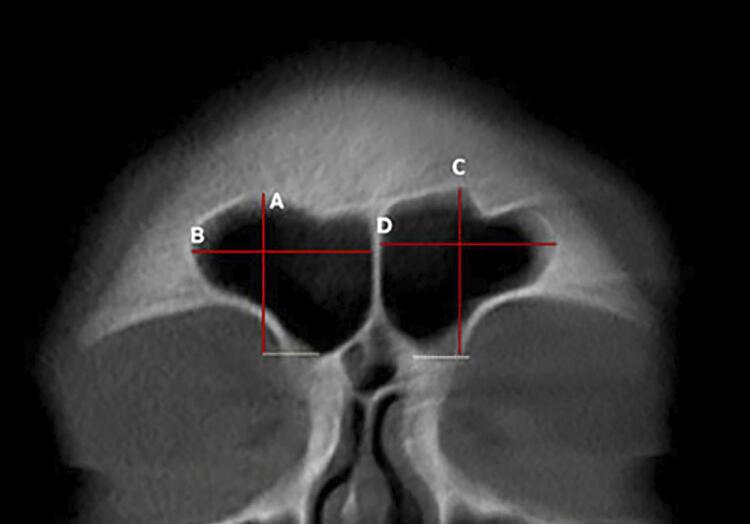

Results: Except for the higher frontal sinus index in females, males exhibited higher numerical values for height, width, and anteroposterior (AP) length. The significance level for all statistical tests was set at 0.05. Multivariate logistic regression identified the following four essential morphometric features: sinus height, anteroposterior length (depth) of the sinus, sinus width, and total sinus width. Both the predictive formula and the ANN demonstrated sexual dimorphism. The accuracy, specificity, sensitivity, precision, and F1- score values were 73.50%, 74.00%, 73.00%, 73.74%, and 73.37% for the regression model, and 76.00%, 84.00%, 68.00%, 80.95%, and 73.91% for the ANN, respectively. Except for sensitivity, the ANN outperformed the predictive formula regarding maximum specificity, accuracy, precision, and F1 score.